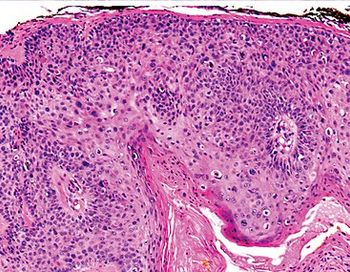

A recent phase 2 study showed promising survival improvements with neoadjuvant Libtayo in patients with cutaneous squamous cell carcinoma after a year and a half follow up.